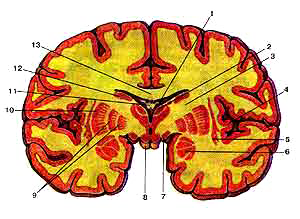

Базальные (подкорковые) умы (nuclei basales) на фронтальном разрезе головного мозга, разрез сделан на уровне сосцевидных тел

1-сосудистое сплетение бокового желудочка (центральная часть);2-таламус;

3-внутренняя капсула;

4-кора островка;

5-офада;

б-миндалевидное тело;

7-зрительный тракт;

8-сосцевидное тело;

9-бледный шар;

10-скорлупа;

11-свод мозга;

12-хвостатое ядро;

13-мозолистое тело.